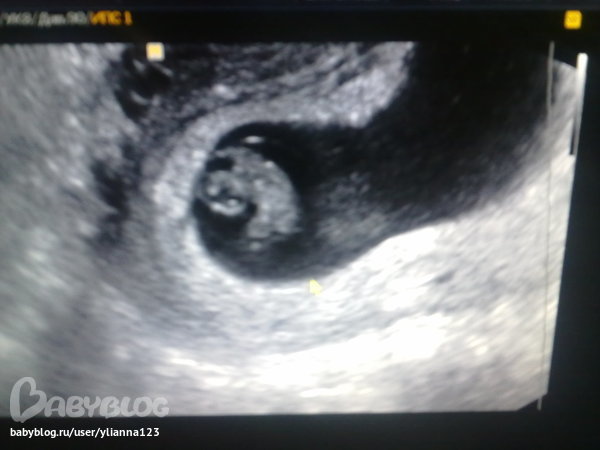

ФолликулометрияСегодня была на УЗИ вот снимок, чт оскажете???

Врач узи ставит ретрохориальную гематому и одно плодное яйцо, может у кого то было что то подобное. Вы тут лечше всех врачей разбираетесь. И срок по узи 5 недель 4 дня, а по М 5 недель